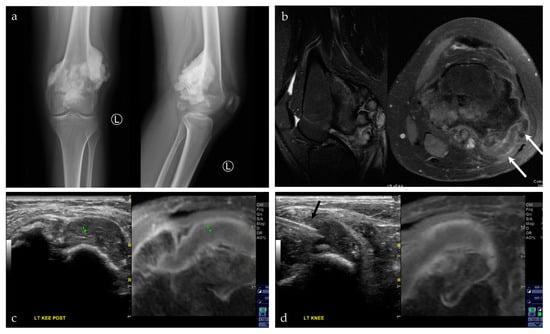

| 18/F | Left posterior knee | US-MRI | Parosteal osteosarcoma, with a chondroblastic component | Neoplastic, malignant |